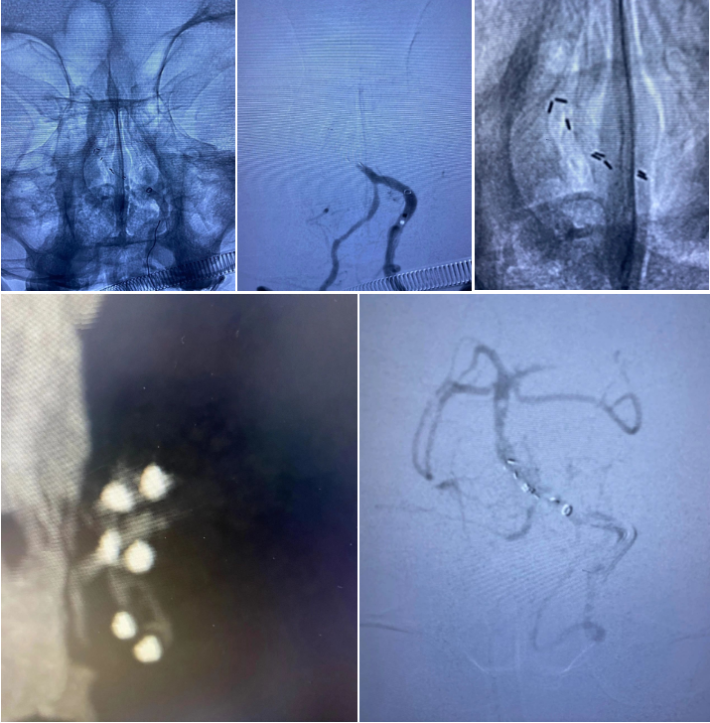

经过尝试,支架导管Rebar 18➕Synchro导丝200cm通过变形严重的原支架Enterprise 2。

打开取栓支架。

Solitaire AB 4mmx20mm成功挂住Enterprise 2。

尝试回收支架至5F Navien,牵扯力量比较大,提心吊胆。

经反复收拉尝试,最终取出Enterprise 2支架。

Enterprise 2支架在血管内两端严重变形,反折的Mark恰好被Solitaire AB支架咬合取出。

Enterprise 2支架经过体外揉搓,恢复了形态,支架内一同取出的还有一大坨增生的支架内血栓。

造影未见出血,血流良好,原狭窄在第一次支架时球囊扩张,现在狭窄已缓解。狭窄远端血管内膜稍不光滑。观察30min,血流稳定,为避免再放支架血栓,同时本次预后尚未知,暂不植入第二枚支撑支架,予以替罗非班注射液应用。